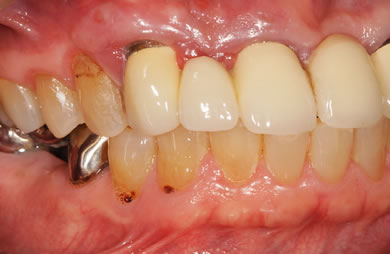

治療後

• 治療後